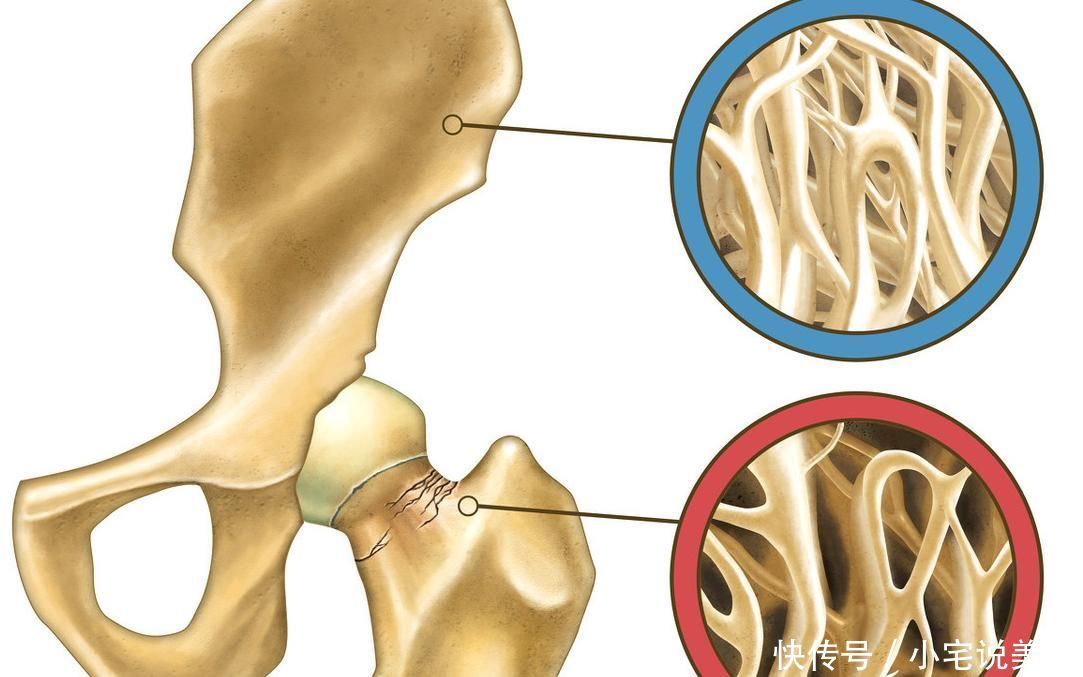

文章插圖

2、身長縮短、駝背

當(dāng)骨質(zhì)疏松出現(xiàn)后,患者可能會有身長縮短的情況,或者是駝背的比較明顯。因?yàn)檫@個時候患者的骨骼已經(jīng)和常人不一樣了,十分的脆弱以及容易彎曲,變形。如果你觀察一些老人其實(shí)就會發(fā)現(xiàn),他們的駝背的比例是很高的。

3、骨折

當(dāng)骨質(zhì)疏松比較嚴(yán)重的時候,患者出現(xiàn)骨折的情況也會增加,因?yàn)楣穷^的骨密度下降了,所以稍微受到一些外界的撞擊,就可能會骨折。因此老人應(yīng)在家里做好防滑的措施,在浴室以及廚房要多加小心,這兩個是很容易摔倒的地方。